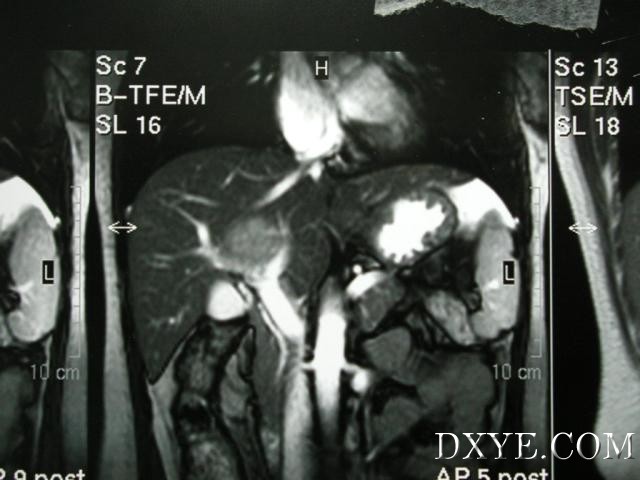

肿瘤

位于左内叶,从位置上看与第一肝门关系密切,患者脾脏肿大AFP>30000,无其他脏器远处转移的迹象,诊断为肝细胞肝癌

从MRI片子可以看出,肿瘤骑跨于左右门静脉之间。